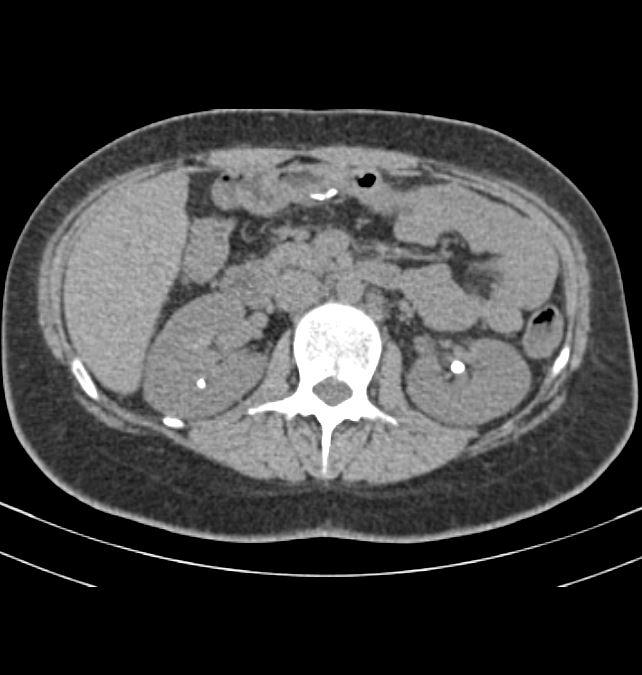

Case of the Week 20 2017 *26-year-old male wiht flank pain, hematuria. What is the most likely diagnosis? Answer Answer: Bilateral nephrolithiasis Kategori:Cases Önceki yazı Case of the Week 16 2017 Sonraki yazı Case of the Week 21 2017